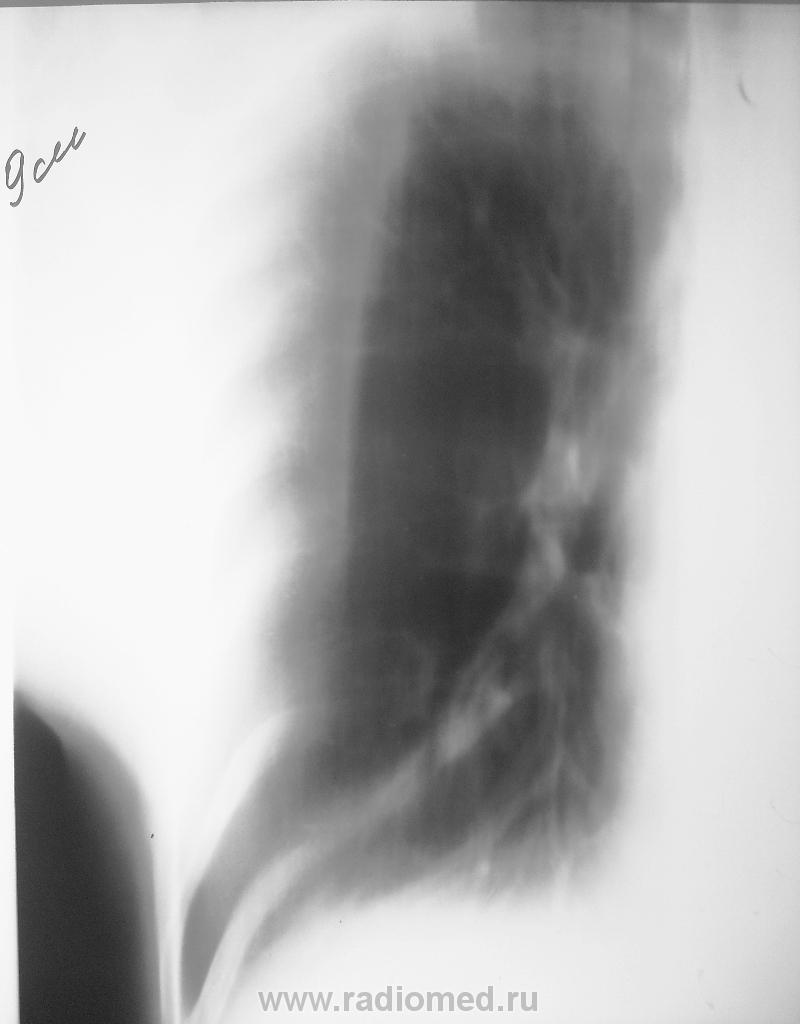

Пациентка госпитализирована через "скорую помощь", впервые выставлен диагноз Sh.. Женщина пьющая, An.vitae - простудные, со слов, на учете по соматическим заболеваниям не состояла, ФЛГ больше 3-х лет назад. Жалоб, температуры  и катаральных явлений нет, кровь без особенностей, назначена Rg. ОГК (по стандарту, нет ФЛГ за последние год). Зацепился глаз и понеслась...

• https://radiomed.ru/sites/default/files/styles/case_slider_image/public/user/7926/9_sm_tomo-pr.jpg?itok=fMptPZDD

Вероятнее всего фиброзные изменения - фиброателектаз. Возможно последствия аспирационной пневмонии. Можно предположить по алкогольному анамнезу. Необходимо дифференцировать с периферичесой опухолью- КТ ОГП, ФБС, рентгенконтроль в динамике на худой случай.

Я посчитала, что тут доброкачественные дела. Но контроль назначила. Посмотрим через 10-14 дней.

Боковая проекция, лично у меня, вызывает уверенность, что стандарт для "пьющих" должен быть соблюден, и прежде всего, надо кинуть эту "Еву" в объятия фтизиатров...